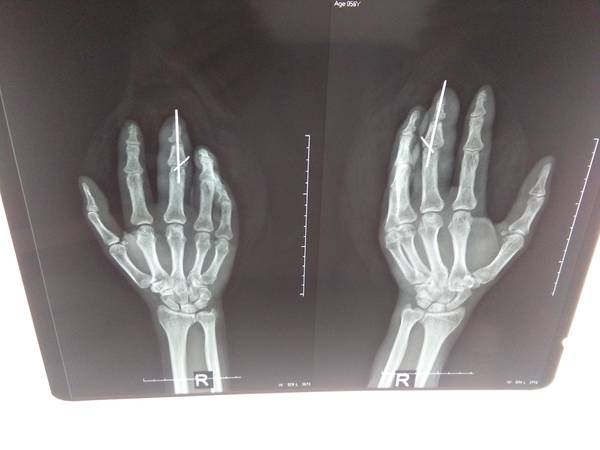

[断指再植] 一例中指套脱离断再植

整个中节及末节近端动脉,背侧静脉移植,屈伸指肌腱没有移植。

2月后复查

IMG_20151130_101249.jpg

IMG_20151130_101253.jpg

IMG_20151130_101254.jpg